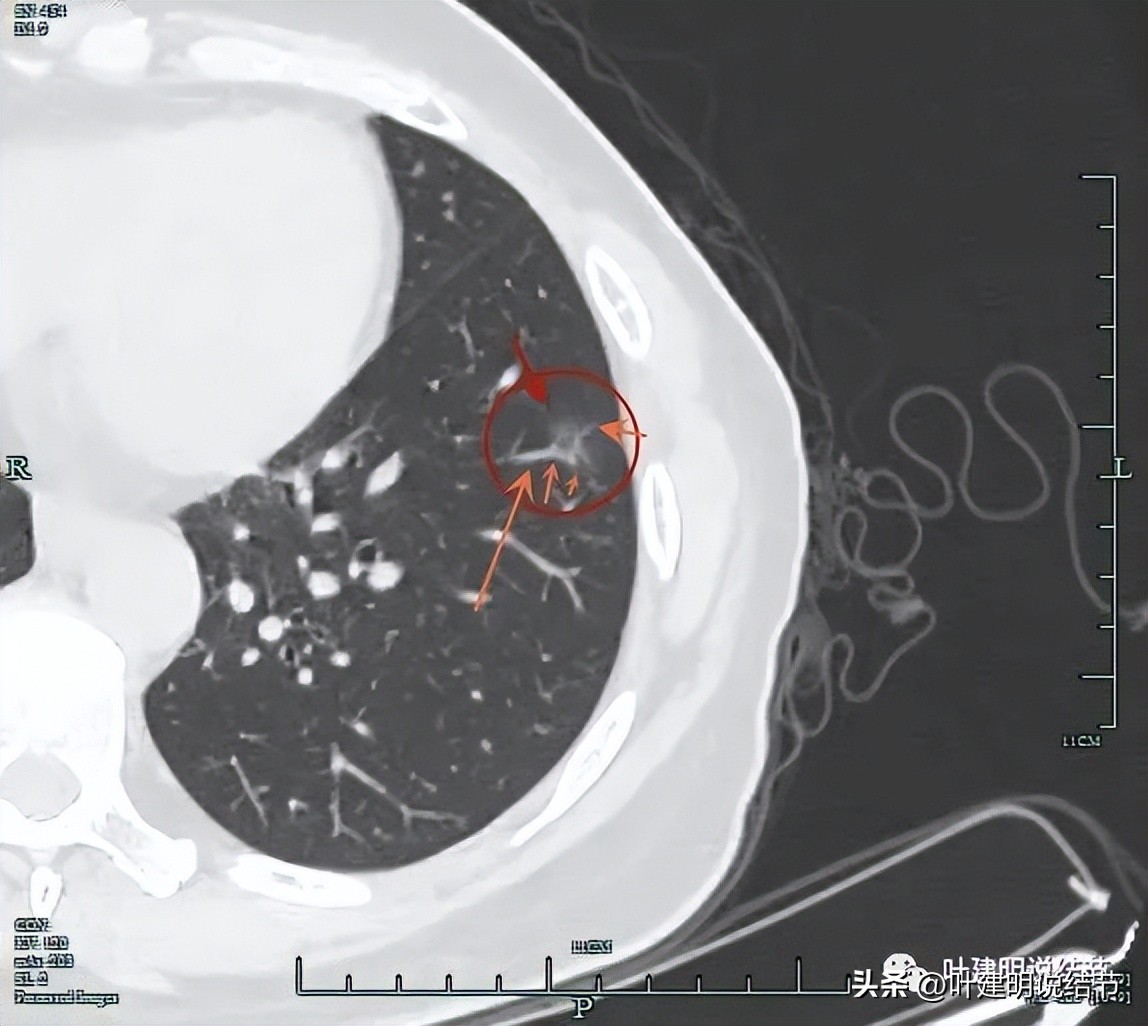

靶重建后发现病灶囊腔型,桔色箭头示进入的血管有异常增粗,而且壁显得毛糙;黄色箭头示空腔;红色箭头示整体轮廓较清;绿色箭头示有磨玻璃成分,虽然密度较低;蓝色箭头示病灶略有胸膜牵拉影响,只是力较弱而已。

上图显示了病灶轮廓与瘤肺边界其实还是清楚的。

部分边缘有毛刺征可见。

显示明显的血管征与血管异常增粗和壁毛糙。

上图显示病灶轮廓较清,有锐利细毛刺征,灶内有弯曲血管穿行。

囊壁有少许是偏实性成分的,如粉色箭头所示。

血管增粗进入并散开来。

血管在病灶内发出分支。